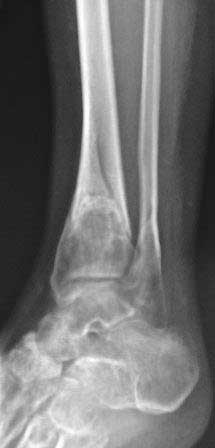

Пациентка 32 года, травму получила в результате ДТП, лечилась в гор.б-це №? Москвы с 19.07.по04.08.11г скелетным вытяжением, после наложена гипсовая повязка,(р-снимок 1,2.) после спадения отека гипс переведена в циркулярную, (видимо на другой вид лечения не хватило средств), гипс снят 19.11.11г(снимок-3) .Жалобы на боли при ходьбе через несколько шагов, увеличение отека в голени и г/стопном суставе, боли ноющего и неприятного характера, хромота, при осмотре отечность голени в с-н/з и г/с суставе, при пальпации умеренная болезненность в н/з голени, подошвенное сгибание в г/с суставе ограничена и болезненна. Работа связана с ходьбой, просить помочь чтобы не потерять работу. Пока в голове только КДО аппаратом Илизарова, уважаемые коллеги помогите советом! Доступно БИОС, пластины DCP. и прилагается последние р-снимки.

Для БИОС перелом "низковат",с DCP возможно потеряет работу."Хороший" аппарат Илизарова оптимальный вариант для нее , ее работы и ее г/стопного сустава.А перелом по-моему внутрисуставной,да?

Нет, это не внутрисуставной, а скорее всего это

43А2,3(2).больная согласна на КДО аппаратом Илизарова, думаю база I,VIII или IX, и надо ли блокировать г/стопный сустав.